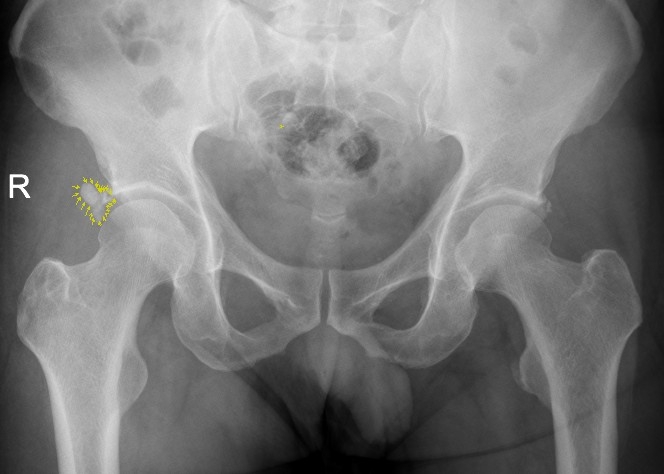

該患者為男性患者,47歲。右髖部疼痛7個多月,曾斷續(xù)就醫(yī),未明確診斷,疼痛時緩時重。入院前兩天,右髖部劇烈疼痛,患髖不能伸直,只能左側(cè)臥位,謂之“坐臥不寧”,需家人攙扶下才能勉強(qiáng)行走。經(jīng)臨床經(jīng)驗(yàn)豐富的骨三科主任、主任中醫(yī)師李彬以“右髖關(guān)節(jié)盂唇病變”收入住院治療,經(jīng)X光核磁共振檢查,患者右髖關(guān)節(jié)盂唇鈣化。

X片顯示盂唇鈣化病灶